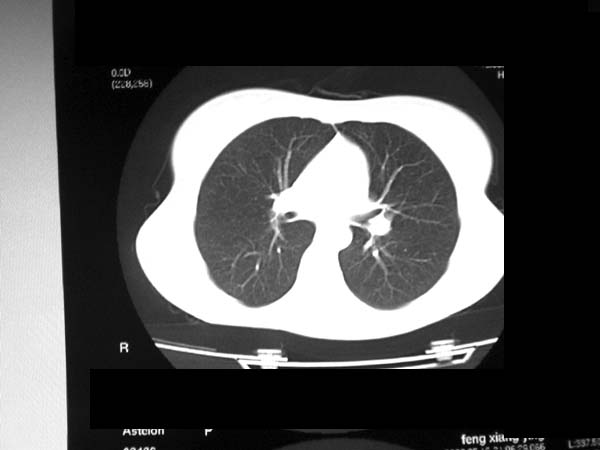

标题: CT13486:F 17Y 咳嗽 咳痰数日请会诊 [打印本页]

标题: CT13486:F 17Y 咳嗽 咳痰数日请会诊

白细胞9600不发烧

考虑右下结核球

右肺下叶结核灶

右下肺背段病灶,考虑结核与炎症鉴别,请进一步检查.

考虑为:右肺下叶外基底段结核球。

结果;痰中找到结核杆菌

痰涂片已找到结核杆菌  将结果告诉大家